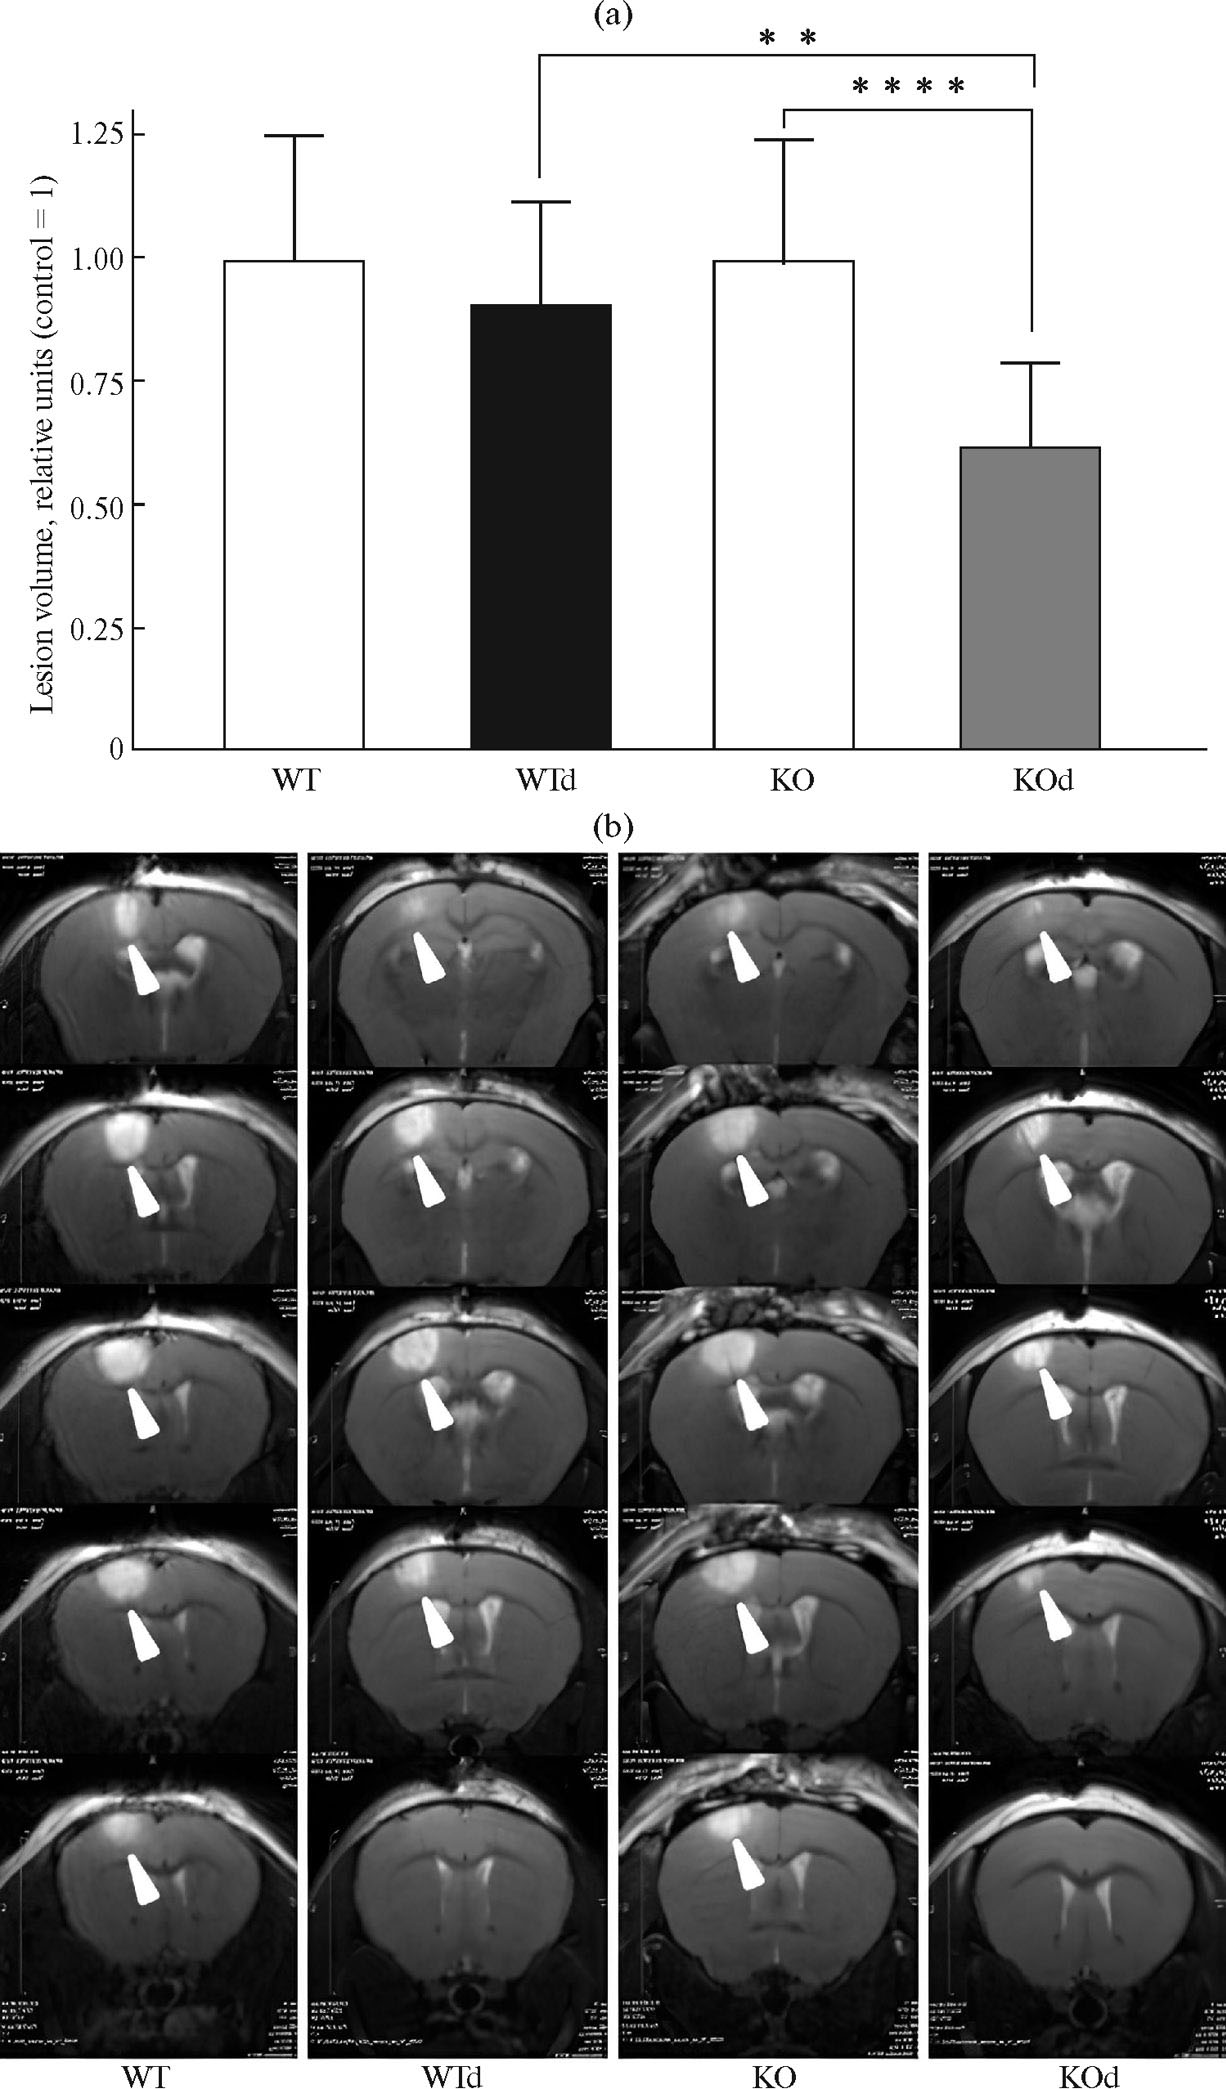

Размер очага повреждения является основным показателем тяжести ишемии. В результате анализа Т2-взвешенных изображений было установлено, что ноĸаут гена Panx1 в 1.5 (1.2–1.7) раза снижал размер очага у животных на фоне 2-недельного диабета (рис. 3). Следует отметить, что у контрольных животных, которым не вводили стрептозотоцин, нокаут гена Panx1 не влиял на размер ишемического очага (рис. 3), не было достоверных отличий и в выраженности ишемического повреждения (всех измеряемых параметров за исключением теста «Решетка») у мышей при сравнении групп дикого типа с диабетом и без него.

Рис. 3. Вызванное фотоиндуцированной ишемией повреждение мозга у мышей дикого типа и с нокаутом гена Panx1 на фоне диабета. (a) – объем ишемического очага поражения после фототромбоза у мышей дикого типа и с нокаутом гена Panx1 на фоне диабета (данные нормированы на средние значения в соответствующих контрольных группах, у животных без диабета (control = 1)), (b) – наглядные Т2-взвешенные МРТ-изображения повреждения мозга у исследуемых групп животных. WТ n = 11, WTd n = 7, КО n = 21, КОd n=13. Различия достоверны: ** – p < 0.01.